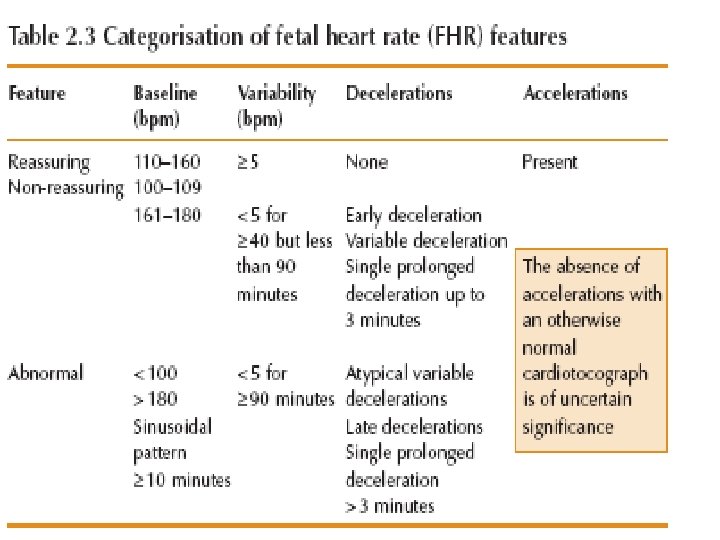

Cardio. Toco. Graphy • Normal • Suspicious • pathological

Categorisation of fetal heart rate traces Category Definition Normal All four reassuring Suspicious 1 non-reassuring Rest reassuring Pathological 2 or more nonreassuring 1 or more abnormal